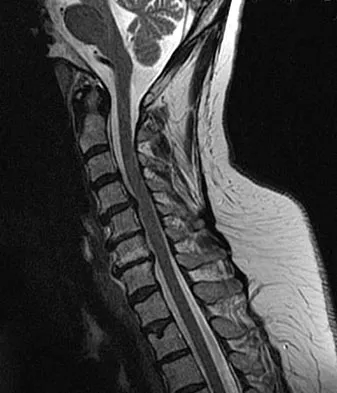

A 65-year-old man with ankylosing spondylitis has neck pain after falling back over his lawnmower, striking his thoracic spine, and forcing his neck into extension. Examination reveals subtle weakness of the intrinsics and finger flexors at approximately 4+/5. Initial management consists of immobilization in a rigid collar, and placing his head in the anatomic position. Radiographs reveal a subtle extension fracture of the lower cervical spine. Approximately 6 hours after the injury, he reports increasing paresthesias in his upper and lower extremities, and examination now shows his intrinsics are 2/5, finger flexors are 3/5, and his triceps are now weak at 4/5 on manual motor testing. In addition, his lower extremities now show weakness in both dorsal and plantar flexion of the ankle in the range of 4/5. Repeat radiographs appear unchanged. An MRI scan is shown in Figure 2. Management should now consist of

Explanation

It is not uncommon for patients with ankylosing spondylitis to sustain extension-type fractures, most typically of the cervicothoracic junction. These fractures can appear nondisplaced or minimally displaced initially, making them difficult to diagnose. Because there is no mobility between vertebrae, fractures tend to occur more like those of a transverse fracture of a long bone. In addition, the vertebral bodies are vascular and their canals are relatively enclosed, making them vulnerable to epidural bleeding. The MRI scan reveals an epidural hematoma located posteriorly on the cord; therefore, the treatment of choice is surgical evacuation and a posterior laminectomy. Because of the intrinsic instability of such fractures at the time of the laminectomy, internal fixation and stabilization with a posterior fusion is warranted. A simple laminectomy will only increase instability, and control is unlikely with halo vest immobilization. An anterior procedure will not effectively treat the problem given the location of the hematoma. Consideration can be given to methylprednisolone and observation; however, this will not eradicate the problem. Bohlman HH: Acute fractures and dislocations of the cervical spine. J Bone Joint Surg Am 1979;61:1119-1142.